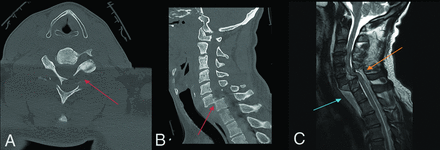

Fracture-positive, radiologist true-positive, CNN false-negative case example. Axial (A) and sagittal (B) cervical spine CT images, and sagittal fat-saturated T2-weighted cervical spine MR image (C) demonstrate a C6–7 fracture-dislocation with cord compression. Red arrows demarcate fracture-dislocation, the blue arrow demarcates prevertebral edema, and the orange arrow demarcates cord compression. This case example illustrates an important drawback of the CNN to overlook areas of gross bony translation, as it was only designed to detect linear bony lucency in patterns consistent with fractures.